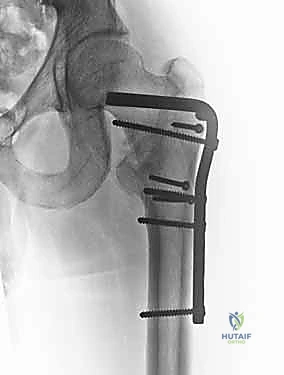

يعتمد اختيار نوع الجراحة على شكل الكسر، مدى تفتته، وجودة عظام المريض. يتقن الدكتور محمد هطيف أحدث تقنيات التثبيت الداخلي العالمية.

| نوع الكسور المناسبة | الكسور المستقرة (Stable Fractures) ذات التفتت البسيط. | الكسور غير المستقرة (Unstable)، المفتتة بشدة، أو التي تمتد لأسفل العظم. |

| الشق الجراحي | شق جراحي جانبي أطول نسبياً (حوالي 10-15 سم). | جراحة طفيفة التوغل، شقوق صغيرة جداً (Minimally Invasive). |

| فقدان الدم | أكثر نسبياً مقارنة بالمسمار النخاعي. | أقل بكثير. |

| سرعة التعافي | ممتازة، ولكن قد تتطلب حذراً أكبر في الكسور غير المستقرة. | أسرع، ويسمح بتحميل الوزن في وقت أبكر في الحالات المعقدة. |

6. التثبيت النهائي (Locking)

لضمان عدم تحرك الغرسة، يتم تثبيتها بمسامير إضافية أصغر في جسم عظم الفخذ. هذه المنظومة الميكانيكية توفر ثباتاً استثنائياً يسمح للمريض بتحريك ساقه فور استيقاظه من التخدير.

مجموعة من الصور الإضافية التي توضح مراحل دقيقة من العمل الجراحي المعقد الذي يجريه الأستاذ الدكتور محمد هطيف لضمان أعلى درجات الدقة الميكانيكية الحيوية: